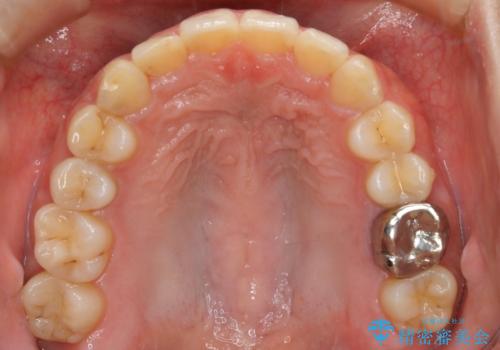

【非抜歯】インビザラインでガタつきと口元を改善!非抜歯でも印象が変わる矯正治療

- 歯のガタつきと口元の突出感を主訴に来院されました。

装置の希望がインビザラインだったため、非抜歯でインビザラインの特徴を最大限に生かして行う矯正治療を選択しました。

顔貌写真でも明らかに口の閉じやすさやEラインが改善している様子が分かります。

一般的に口元を下げるための治療というと抜歯矯正を思い浮かべる方が多いかと思います。そもそもガタつきを治したり歯を引っ込めるためのスペースの作り方には大きく分けて4種類の方法があります。

①抜歯 ②歯列の幅の拡大 ③IPR(歯の幅を削って小さくする) ④歯の後方移動 です。

インビザラインの登場により抜歯以外の3種類の方法を効率よく活用することができるようになりました。

そのため、非抜歯でも口元の環境が改善するケースがあります。